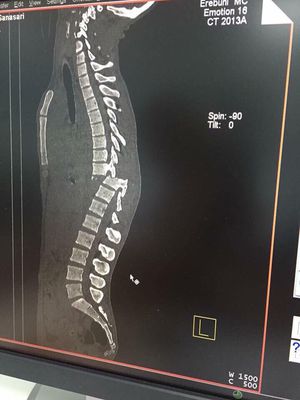

Fracture

Ct

Vertebrae

disc prolapse.... π―π―